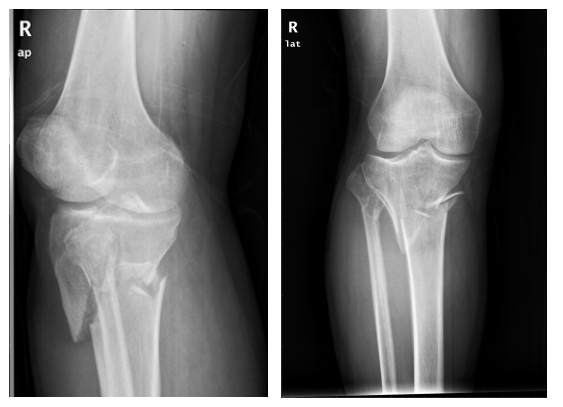

骨折是我们在日常生活中常见的一种疾病,通过手术治疗往往可以达到稳定的固定作用。手术固然重要,但术后功能康复亦不能忽视。小编最近就遇到一位胫骨平台骨折患者,该患者在4个月前发生了车祸导致胫骨平台骨折,并进行切开复位内固定手术治疗。但由于在术后一直畏痛少动,未进行积极地康复治疗,致使患侧膝关节难以像健侧一样伸直,下肢功能急剧下降。为了避免出现以上情况,今天小编就与您分享,胫骨平台骨折术后该如何正确康复。

胫骨平台是膝关节重要的负荷组成部分,也是膝关节创伤中最常见的骨折之一,多发生于强烈的外翻和内翻应力合并轴向载荷时,同时股骨髁对其下胫骨平台有压力和剪切力,可造成劈裂骨折、塌陷骨折或两者兼有。当发生胫骨平台骨折后,需要通过手术切开复位固定,术后要及时进行康复训练,以加快骨折愈合,促进患肢功能恢复。

1.拍摄膝关节X光片复查,并根据骨折线愈合情况及专业医生建议决定是否开始进行患肢负重练习。